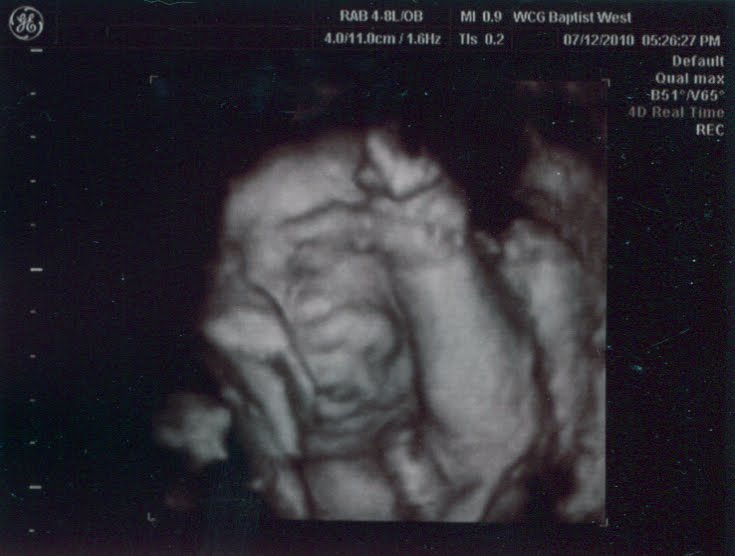

Now you know why I’ve been so quiet here lately: It’s been…